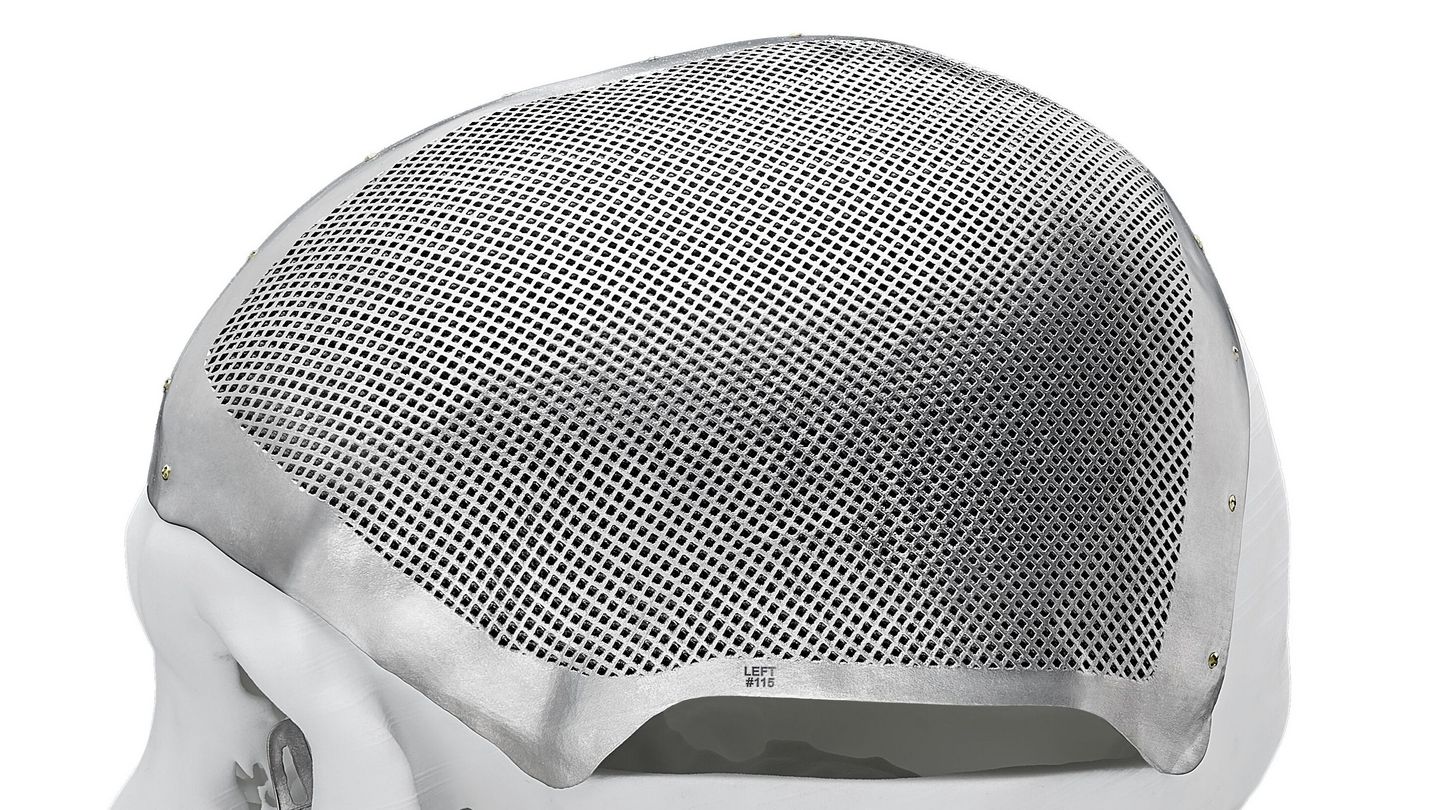

Additive manufacturing of personalised implants for craniofacial applications

Tumour patients and patients with congenital or acquired malformations caused by trauma or atrophy often benefit greatly from an individualised patient solution (IPS). Additive manufacturing now makes it possible to produce high-quality implants with fast availability at acceptable costs – even for one-off lot sizes. Optimum patient care is guaranteed. The implants are based on the patient's anatomical data, which means faster recovery and significantly fewer surgical procedures. In many cases, the implant can even be subjected to loads immediately after surgery.

Benefit from individualised part design adapted to the patient's anatomy. Lattice and porous structures can also be incorporated into the implant to improve fluid and heat exchange.

Examples of personalised implants in oral and maxillofacial surgery